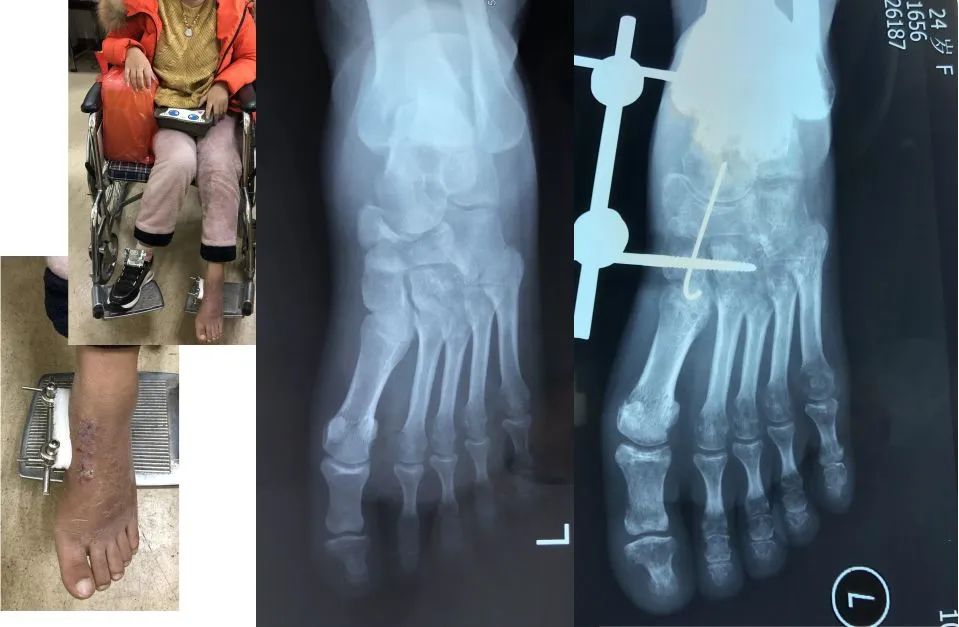

24岁因故骨折50天没有负重,出现严重的骨质疏松。